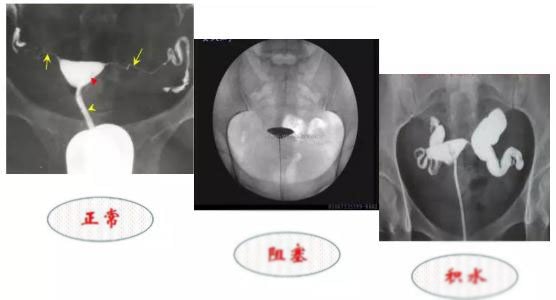

造影是最常用的检查方法。造影是在X线透视下进行,通过导管经阴道向子宫腔及输卵管内注入造影剂,观察造影剂在输卵管及盆腔内的显影情况来了解输卵管是否通畅,以及了解阻塞的部位及宫腔形态。

输卵管造影的结果